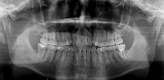

Background: Impaction of mandibular third molars (M3) is one of the most common diseases. Extraction of M3 usually exacerbates osseous defects at the distal aspect of the adjacent second molar (M2). BonMaker® ATB has been cited as a novel autogenous bone grafting material. The aim of this pilot study was to introduce a novel method for repairing the distal osseous defects of M2 after the surgical removal of M3 with autogenous tooth graft powder (ATGP).

Method: A total of five patients were enrolled in this prospective split-mouth clinical pilot study. Four impacted wisdom teeth were extracted bilaterally from each patient with proximal alveolar bone loss ≥ 5 mm of M3. The ATGP was prepared chairside from two extracted one side third molars and randomly implanted in one of the M3 extraction sockets, and the other side was treated with a blank and considered the control site. Patients were followed up at 6 months.

Results: The five patients included three males and two females. Their ages ranged from 25 to 30 years, with a median of 27 years. Primary wound healing without complications was achieved in all the patients. There was a greater tendency for swelling of the cheeks and trismus to occur at the experimental site on the third postoperative day. Compared with the control site, the experimental site exhibited progressive bone filling and ossification in the sixth postoperative month. Moreover, the probing pocket depth of the experimental site was lower than that of the control site.